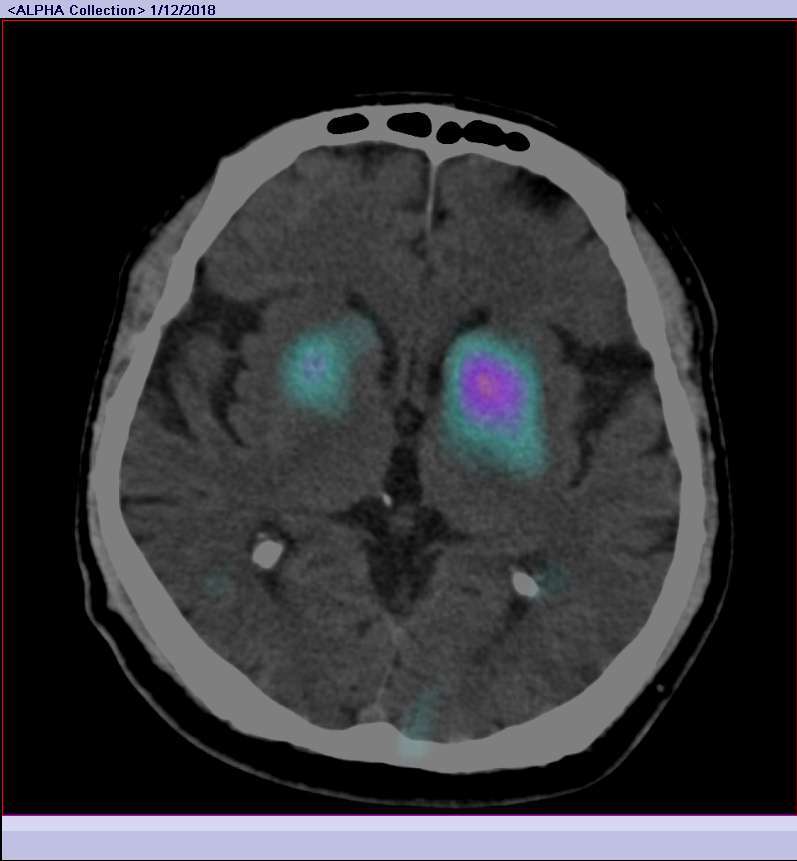

Dementia